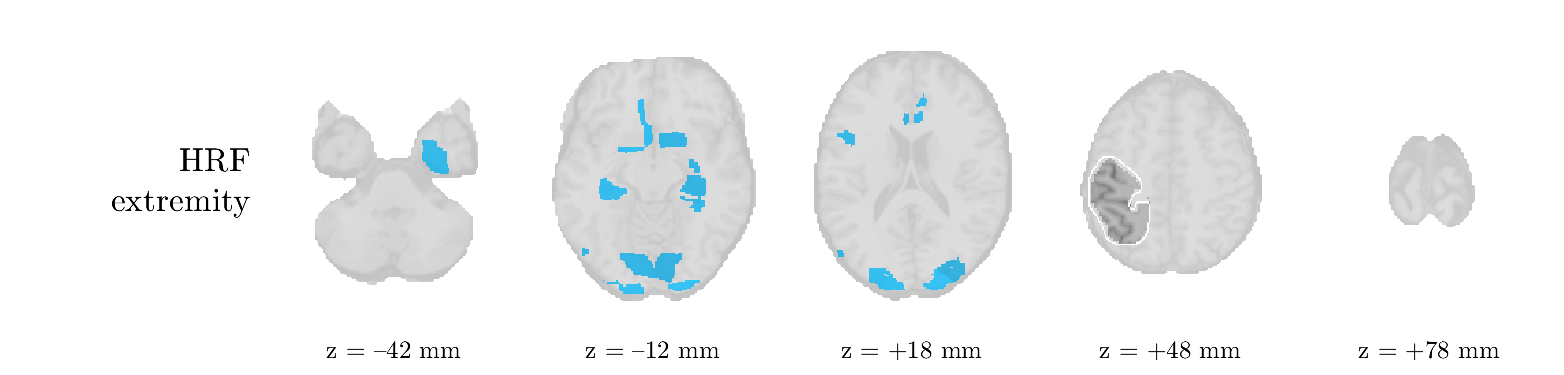

Patient 2

We analyze the solution with sources, and show the results in Figure 3 and 4. As for patient 1, we found a source which is strongly correlated to the MWF envelope, and which had a mostly low-frequency behavior characteristic for spikes. The topography is mostly uninformative, and does not clearly correspond to the patient’s clinical data. The third source is mostly present at both sides of the head, is very sparsely active in time, and has a high-frequency content: this is most likely an artifact due to the neck muscles. Again, there is one of the highest-entropy HRFs which belongs to a ROI in the IOZ. Now, the waveform is clearly resolved from the other HRFs, through the strong initial dip (before 0 seconds). Such a dip is sometimes observed in HRFs, but its underlying physiological mechanism is not yet fully understood. It is possible that this dip reflects altered vascular autoregulation near the IOZ (cfr. the explanation in the Section 1 of the main text), or a rapid depletion in oxygen due to IED generation (before the IED becomes visible on the EEG). Figure 4 furthermore shows that the IED-related component is significantly active in parts of the IOZ, and deactive in others. As mentioned earlier, this deactivation may or may not be due to errors in sign correction. Interestingly, the ROI with the high alteration in neurovascular coupling is distinct from both the activated and deactivated ROIs.